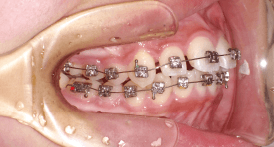

After Bracket - ブラケット装着4ヶ月経過 -

カリエールモーションをはずしたその日に、ブラケットとワイヤーを装着し、4か月経過の状態です。当院ではここでは主にインビザラインを使用します。